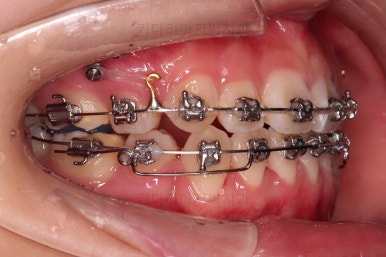

조심스럽게 앞니를 뒤로 뒤로 당겨줍니다.

이번 환자분은 특히나 옥니가 되지 않도록 매우 주의해야 하는 경우였고, 아래 턱끝 힘이 센 분이기 때문에 아래 앞니가 옥니가 될 가능성이 매우 큰 분이었어요.

윗니는 당겨넣을 양이 아직 많고, 아랫니는 앞니 각도 조절(옥니가 되지 않게)을 매우 다양한 테크닉으로 해 나갑니다.